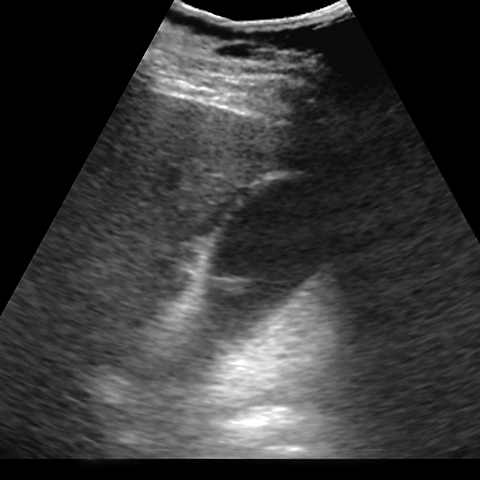

40-year-old obese female presents with colicky right upper quadrant pain [1 of 2]